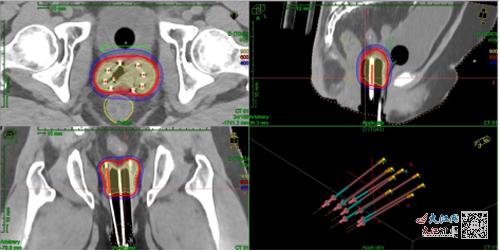

圖為后裝靶區及劑量

3D打印后裝模具制作主要包括圖像采集、預計劃制定、3D模具設計及打印等過程,設計完成經醫生確認后,將數據傳至3D打印機,使用PLA材料打印出模具。3D打印模具可以降低操作難度,減小重復誤差,降低膀胱及直腸的近期發生不良反應情況,通過預計劃設置插植針道,避免周圍器官損傷,控制插植針進針方向及深度、降低插植技術難度,彌補通用施源器不足之處。在對臨床上因腫瘤位置及解剖結構等導致施源器放置困難的患者,多項研究均證實3D打印模板的劑量學優勢。